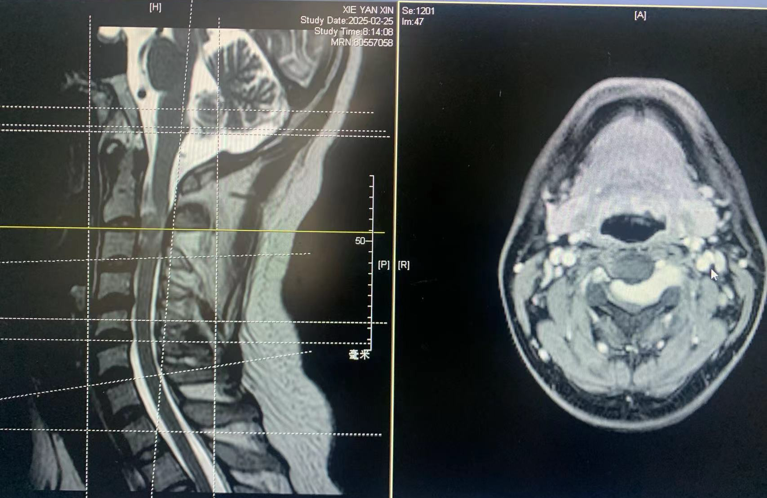

经过检查,他被诊断为颈2/3节段哑铃型神经鞘瘤,肿瘤严重压迫脊髓的右侧并从脊髓腹侧侵犯到左侧,随时可能造成不可逆的瘫痪。

高位颈2/3哑铃型肿瘤

从左侧经脊髓腹侧延伸到右侧压迫脊髓

手术后核磁共振证明肿瘤完全切除,脊髓恢复,没有脑脊液漏